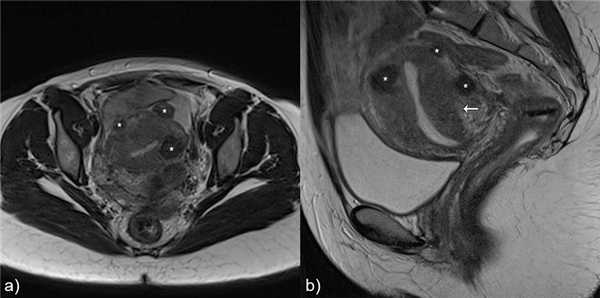

а) Аденомиома и лейомиома

Основной дифференциальный диагноз с лейомиомой.б) Изолированная/ювенильная кистозная аденомиома и accessory cavitated uterine mass - ACUM (термин не имеет адаптированного перевода на русский язык)

Рис.13 Аденомиома: а) сагиттальный Т2 и b) аксиальный Т2-взвешенные изображения, неоднородная гипоинтенсивная на T2 масса с плохо определенными границами, мелкими гиперинтенсивными фокусами в структуре (белые стрелки).

![]()

Рис.14 Лейомиома: а) сагиттальный Т2 и b) аксиальный Т2-взвешенные изображения, неоднородная гипоинтенсивная на T2 масса с четко определенными границами, масс-эффектом на окружающие ткани (звездочка). Есть также особенности, наводящие на мысль о аденомиозе.

Рис.15 Наружный аденомиоз: корональные T2 взвешенные изображения, субсерозная плохо отграниченная масса с низкой интенсивностью сигнала, мелкими гиперинтенсивными фокусами в структуре в левой стенке матки (белая стрелка), имитирующая эндометриоз. Также видны лейомиомы (звездочки).